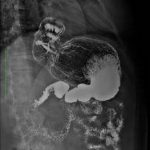

Rayos-X

Los rayos X, o radiografía, utilizan una dosis muy pequeña de radiación ionizante para producir imágenes de las estructuras internas del cuerpo. Los rayos X son la forma más antigua y más frecuentemente utilizada de las imágenes médicas. Se utilizan generalmente para ayudar a diagnosticar huesos fracturados, para buscar una lesión o infección, y para localizar objetos foráneos en el tejido blando

Estudios Especiales